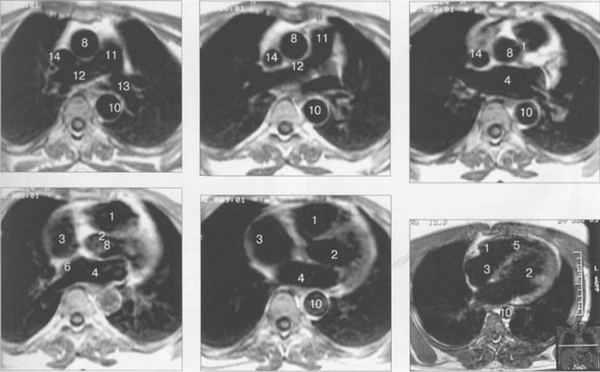

МРТ АНАТОМИЯ СЕРДЦА

МРТ позволяет получать изображения сердца в поперечной (аксиальной), фронтальной (корональной) и сагиттальной плоскостях (ортогональные сечения). Поскольку анатомические оси сердца и магистральных сосудов (за исключением аорты в нисходящем отделе и полых вен) не совпадают со стандартными ортогональными плоскостями исследования, общепринятыми при исследованиях других органов и систем организма, для МРТ-исследования сердечно-сосудистой системы разработаны дополнительные наклонные срезы (двухкамерное сечение, четырехкамерное сечение, сечение по короткой оси левого желудочка).

Рис. 9.47. МРТ сердца. Аксиальная плоскость.

Здесь и на рис. 9.48—9.52:

I — правый желудочек, 2 — левый желудочек, 3 — правое предсердие, 4 — левое предсердие, 5 — межжелудочковая перегородка, 6 — межпредсердная перегородка, 7 — задняя стенка левого желудочка, 8 — восходящая часть аорты, 9 — дуга аорты, 10 — нисходящая часть аорты, 11 — легочный ствол, 12 — правая легочная артерия. 13 — левая легочная артерия, 14 — верхняя полая вена, 15 — нижняя полая вена, 16 — трахея.

На рис. 9.47—9.52 представлены Т1-ВИ наиболее часто используемых МР-сечений сердца.